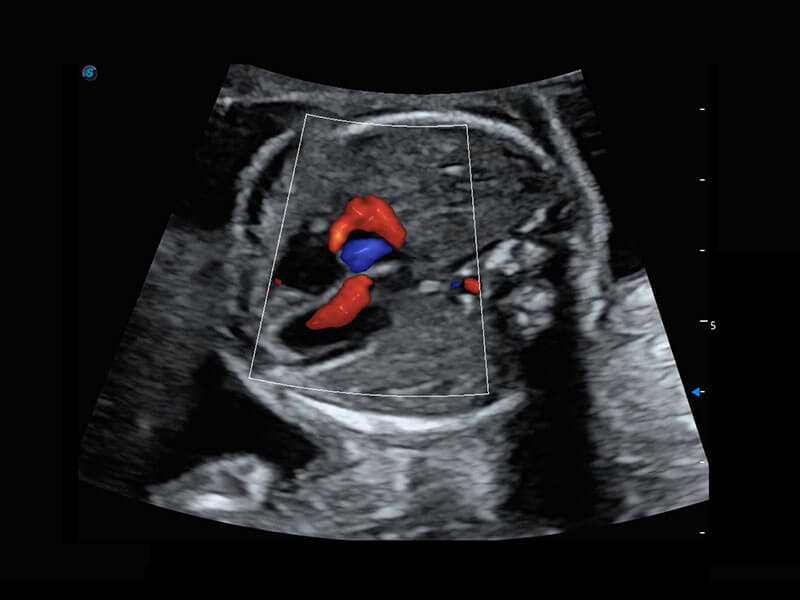

胎心筛查

P60搭载一系列胎儿心脏成像技术,实现精细的胎儿心脏评估。

• 四腔心血流

• 右室双出口

• 胎心容积成像